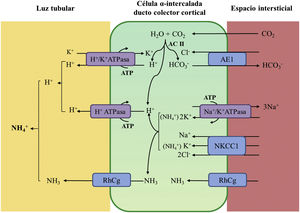

La acidificación tubular distal de la orina en condiciones fisiológicas se resume en la figura 1. La H+-ATPasa (V-ATPasa) es una bomba de protones altamente conservada que se expresa en las células α-intercaladas y que está formada por dos dominios, V1 y V0. Los defectos en la actividad de la bomba H+-ATPasa causan la mayoría de los casos primarios de ATRd de herencia autosómica recesiva. Son debidos a mutaciones en los genes ATP6V1B1,ATP6V0A4 (tabla 1) que codifican las subunidades B1y A4 de la bomba H+ ATPasa, respectivamente4–6. La ATRd de herencia autosómica recesiva asociada a sordera puede ser producida por mutaciones en el gen FOXI 1 que codifica un factor de transcripción que es necesario para la expresión de al menos 4 subunidades de la H+-ATPasa (A1, B1, E2 y a4)7. Un cuarto gen, WDR72 (OMIM 613211), cuando está mutado produce otra variedad de ATRd autosómica recesiva; este gen parece estar implicado en el tráfico intracelular de proteínas reguladoras del equilibrio ácido-base provocando su retención intracelular o un direccionamiento erróneo8,9. Con relación a las manifestaciones extrarrenales: 1) los pacientes con ATRd recesiva causada por mutaciones en los genes ATP6V1B1, ATP6V0A4 pueden presentar una sordera de percepción de manera frecuente y constante en las mutaciones del gen FOXI 1, siendo de inicio temprano y asociado al síndrome de Pendred (ORPHA:705)8, y 2) los pacientes con ATRd recesiva causada por mutaciones del gen WDR72 pueden presentar una amelogénesis imperfecta.

Acidificación de la orina distal en condiciones fisiológicas. La acidificación de la orina tiene lugar en los túbulos distal y colector a través de 3 procesos relacionados: a) reabsorción de la cantidad residual de bicarbonato (10%), que no ha sido recuperada en zonas más proximales de la nefrona; b) titulación del anión fosfato divalente (HPO42−) con H+ que se transforma en anión fosfato monovalente (H2PO4−) o acidez titulable; c) acumulación de amoniaco (NH3) intraluminal que capta H+ y forma amonio (NH4+). La secreción de H+ y la titulación de los tampones urinarios da lugar a la acidificación de la orina con lo que se pueden alcanzar valores de pH cercanos a 4,5 en condiciones de estimulación máxima del proceso. Este hecho se realiza en las células α-intercaladas que se localizan en el túbulo contorneado distal tardío, el túbulo conector y en los ductos colectores corticales y medulares.

La secreción distal de H+ genera una cantidad equimolar de bicarbonato. Por cada molécula de hidrogeno que se excreta a la luz tubular, se genera intracelularmente una molécula nueva de bicarbonato gracias a la acción de la anhidrasa carbónica intracitoplásmica (AC tipo II), que es transferida a la sangre mediante el intercambiador de aniones Cl−-HCO3− (AE1). Las células α-intercaladas secretan H+ por medio de la ATPasa vacuolar (H+-ATPasa) que transfiere H+ activamente a través de la membrana luminal y la H+-K+-ATPasa que intercambia H+ por potasio. La función de la H+-ATPasa está marcadamente influenciada por la electronegatividad generada en la luz tubular por el transporte simultáneo de Na+ en las células principales del ducto colector. La acumulación de NH3/NH4+ en la médula genera un gradiente de concentración que favorece su entrada por la membrana basolateral de las células intercaladas-α. La excreción de NH3/NH4+ requiere de al menos 2 pasos, a saber, ingreso basolateral y excreción luminal. La captación desde el intersticio del NH3/NH4+ se lleva a cabo por varias vías que incluyen el transportador Na+/K+/2Cl− (NKCC1), la Na+-K+-ATPasa (en el caso de estos dos trasportadores, el NH4+ puede ser transportado en lugar de potasio), los canales de gases Rhcg (human Rhesus C glycoprotein) y los canales de NH4+ activados por hiperpolarización HCN (hyperpolarization-activated cyclic nucleotide-gated cationic non-selective). La membrana luminal tiene una alta permeabilidad para NH3. Los canales RhCG están presentes en la membrana luminal y en la membrana basolateral.

En el lado basolateral solo se ha descrito un tipo de ATRd de herencia autosómico dominante (tabla 1) en la mayoría de los casos, que está producido por mutaciones en el gen SLC4A1 (OMIM 109270) que codifica las 2 isoformas del intercambiador de aniones Cl−-HCO3, la isoforma renal también conocida como kAE1 (kidneyanion exchanger 1) y la isoforma de los hematíes también conocida como proteína banda 3 (erythroid isoform o eAE1); kAE1 es responsable de la reabsorción de HCO3− junto con la excreción de Cl− en las células α-intercaladas10 (fig. 1). Este tipo de ATRd, se ha asociado a formas de presentación clínica menos graves, con inicio tardío en la infancia, adolescencia y en pacientes adultos, con menor impacto en el crecimiento comparado con las formas de herencia autosómico recesiva8.